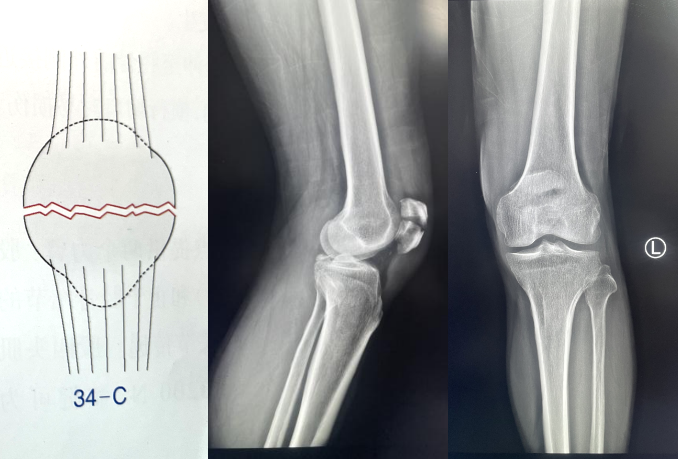

髌骨骨折只占全身骨折的 1%,治疗方式的选择和并发症的防治尤其要注意,急诊来了髌骨骨折患者,你怎么处理?髌骨是人体最大的籽骨,位于膝关节伸膝装置内。解剖特点包括近端宽大的基底和关节外的远侧尖端,前面位于关节外,后面为关节面。股直肌和股中间肌止于髌骨基底部,股内侧肌和股外侧肌止于髌骨的两侧。髌腱起于髌骨尖端,止于胫骨结节。髌骨骨折约占所有骨折的 1%,主要由直接暴力造成,如跌倒时跪地或膝关节屈曲时受到打击。典型的体征包括关节肿胀、压痛、伸膝功能部分或完全丧失。除以主诉和典型体征外,膝关节 X 线片也是必不可少的一项辅助检查,以膝关节正侧位 X 线片最常见,如果怀疑纵向骨折,膝关节屈曲 45° 时髌骨 30° 切位片可以辅助诊断。对于骨折不愈合、畸形愈合所致的关节面不平整以及髌股关节对应关系不良可采用 CT 检查。MRI 有助于诊断软骨缺损和损伤。34-B 型(部分关节内骨折,伸膝装置完整,如纵行骨折)髌骨下极骨折袢钢板结合克氏针、张力带固定 图源:作者提供

拉力螺钉加张力带钢丝固定或经胫骨结节绕髌环扎;经骨缝合撕裂的肌腱加髌骨和胫骨结节间钢丝环绕以加固缝合;袢钢板固定。无移位采用非手术治疗;移位并且单纯骨折采用横向拉力螺钉固定,骨质疏松患者需加环扎固定;对于多骨折块(星状)则采用髌骨环扎加张力带进行固定。克氏针加张力带钢丝;有第三个骨折块则采用拉力螺钉或克氏针加张力带钢丝固定;对于 4 个或 4 个以上的骨折块采用克氏针加螺钉加张力带钢丝进行固定;对于严重粉碎和软骨面广泛破坏的髌骨骨折,髌骨部分或完全切除也是一种可行的办法。